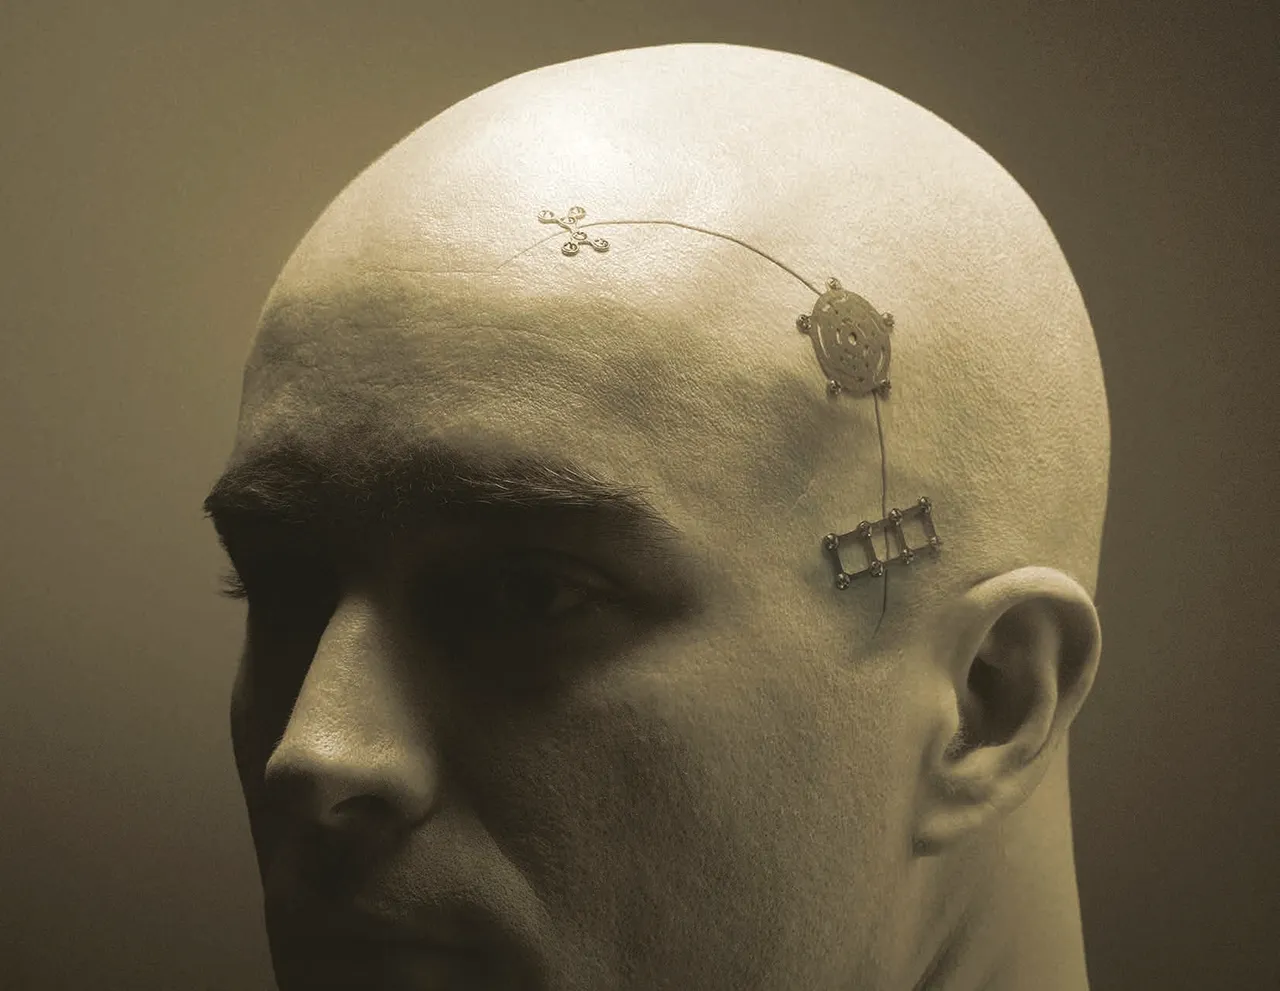

Cierre Craneal

Con un perfil de placas y tornillos de 0.3 mm, el sistema de recubrimiento ThinFlap de...

Cierre de Trépanos

El sistema proporciona un enfoque simplificado para la fijación craneal, lo que reduce...

RapidFlap

El sistema RapidFlap LS es un dispositivo de fijación de craneotomía reabsorbible de...